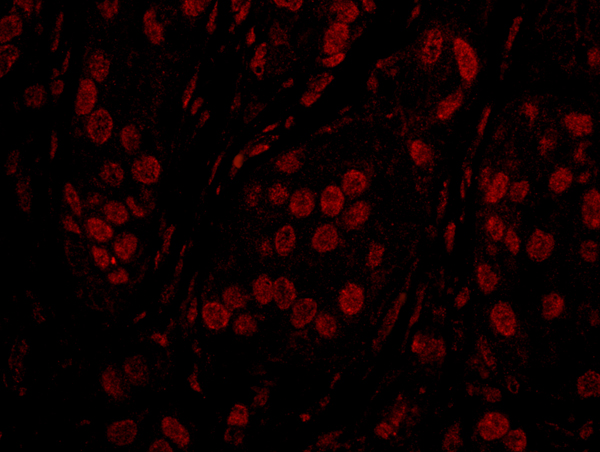

(Detection of human TOPORS by immunohistochemistry. Sample: FFPE section of human breast carcinoma. Antibody: Affinity purified rabbit anti-TOPORS (Cat. No. AAA214115) used at a dilution of 1:100. Detection: Red-fluorescent goat anti-rabbit IgG-heavy and light chain cross-adsorbed Antibody DyLight 594 Conjugated used at a dilution of 1:100.)